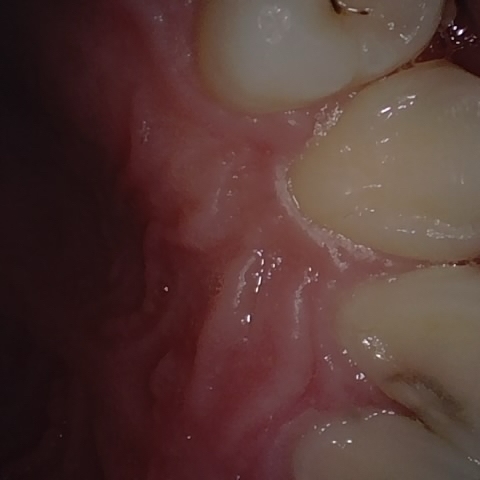

Annotated as "Good"